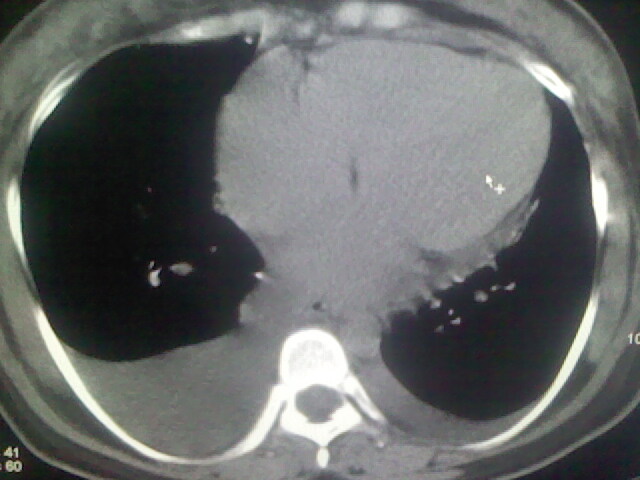

女,24,剖腹产后,突觉胸痛,干咳,不能平卧

做个增强的 ct吧 pte(肺血栓栓塞)不能除外啊 在结合心电图 看看v1-v4导连的t波及st段改变。

患者允许的情况下建议进行心脏超声检查

产后心衰

肺水肿,双侧胸腔积液,心影增大.考虑妊娠心脏病

风心、心衰。两肺水肿、感染灶及胸水是心衰表现